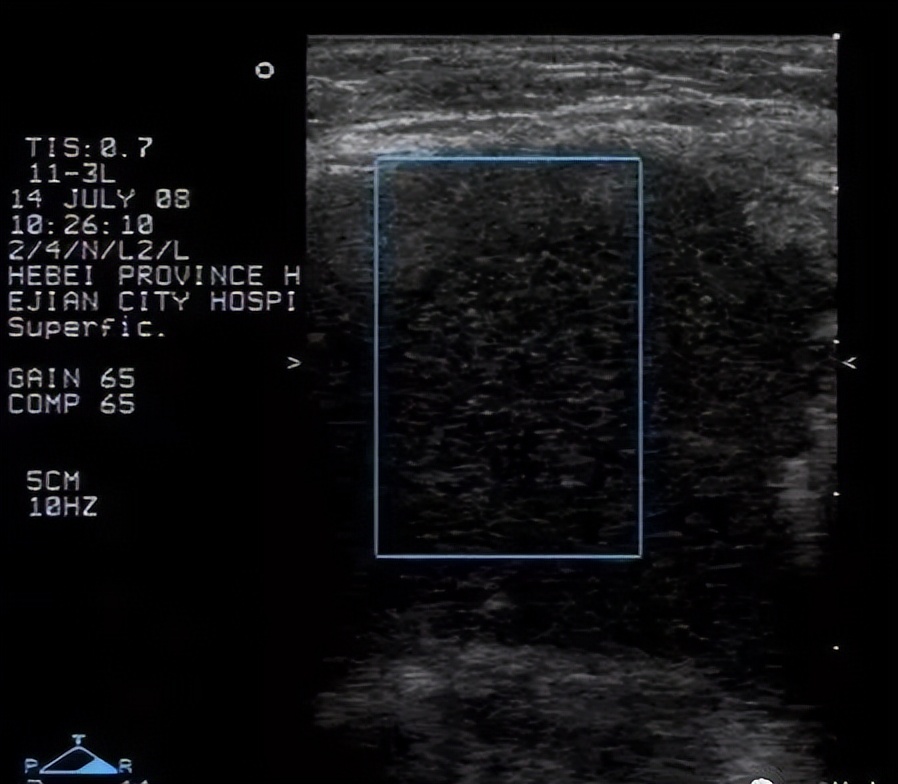

4. 腋下脂肪瘤:超声表现为浅筋膜层见椭圆形肿物,长轴与皮肤平行,内部回声为等回声及强回声,并可见带状或羽毛状强回声,内部一般未见血流信号。